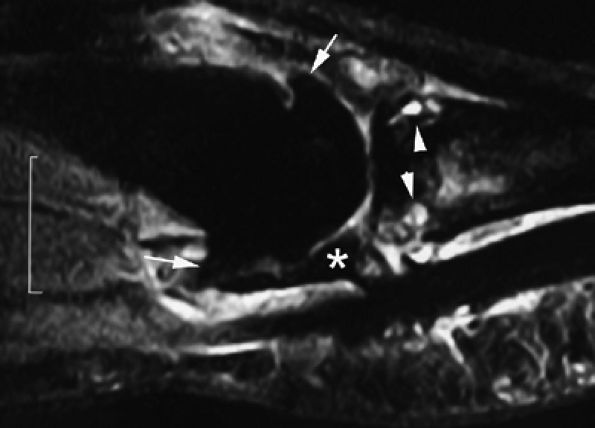

FIGURE 11.20 ● Acute injury of the radial collateral ligament (RCL) of the PIP joint of the fourth finger. Coronal (A) and axial (B) post-contrast fat-suppressed T1-weighted images displaying distal avulsion of the RCL with a proximal retraction (black arrows). The retinacular apparatus is displaced (arrowheads) with periligamentous edema. The ulnar collateral ligament is also identified (white arrows).